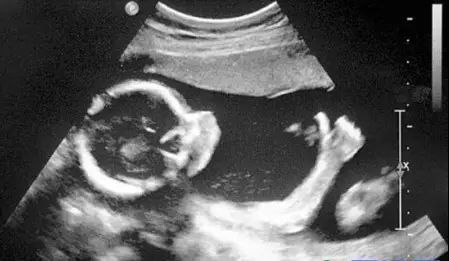

B超:敲一敲,通过声波判断疾病

原理:用超声波穿透人体,当声波遇到人体组织时会产生反射波,通过计算反射波成像。

优点:多方位观察,实时成像。

缺点:超声受气体干扰很大,对于肠道等含气较多的器官,超声诊断准确率会降低,所以一般肠道检查使用肠镜。

B超的原理是利用人体组织对超声波的回声不同,来判断正常组织和病灶的性质。B超和之前提到的三项检查有着较大的区别,但是因为B超机的探头掌握在B超医生的手上,指哪打哪,因此相对更依赖于检查医生的经验。

B超对于人体管腔的液体流动和腹腔脏器检查的敏感性较高,我们常常遇到的胆囊结石,肾结石,血管狭窄,心脏功能等等检查,都是B超的用武之地。B超有着独特的优势,便携,可以在床边,甚至在手术中使用。此外,B超市利用超声波成像,也没有所谓的辐射。所以孕妇多采用B超检查。